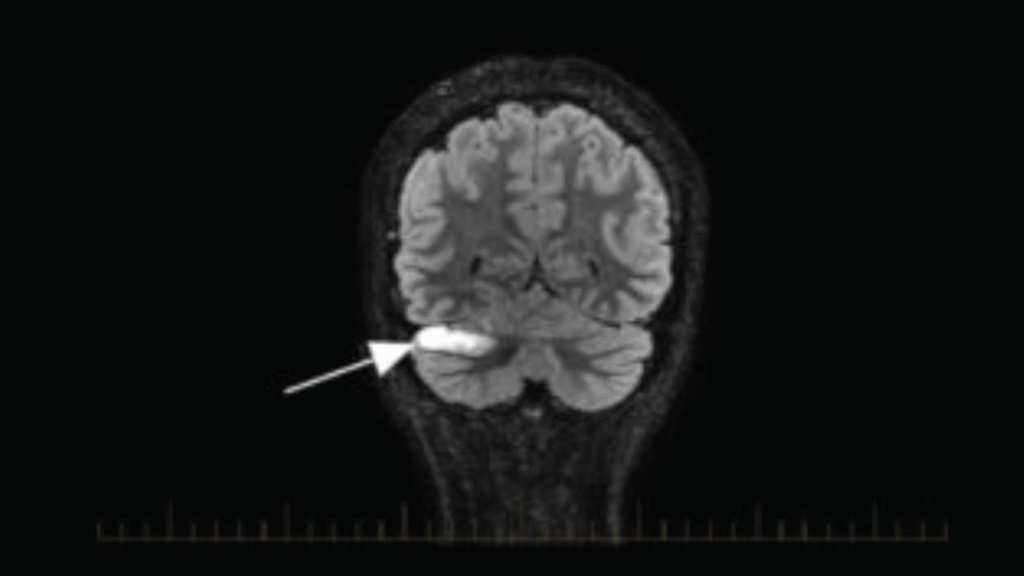

Magnetic Resonance Imaging Predictors of Atrial Fibrillation in Cryptogenic Stroke Cases

Understanding the origin of an ischemic stroke is key in both providing effective treatment and in implementing protective measures to avoid recurrence of stroke. Approximately 25% of ischemic strokes are determined to be embolic strokes of unknown source, where it is difficult to determine whether or not the source is cardioembolic (related to an embolus within the heart). Methods such as administration of anticoagulants or long-term cardiac monitoring can be employed in order to help prevent stroke recurrence when the source of the stroke is defined as cardioembolic. It is theorized that a definable imaging pattern with lesions in multiple vascular territories (MVT; multiple areas in the brain) correlates to strokes of cardioembolic origin. This study aims to develop and validate methods for imaging and identifying MVT in order to more accurately identify strokes with likely cardioembolic sources where preventative measures can be implemented to avoid another stroke. Implications of validating this method of identifying an acute brain imaging biomarker include a reduction in secondary stroke rate, death, disability, and healthcare costs.